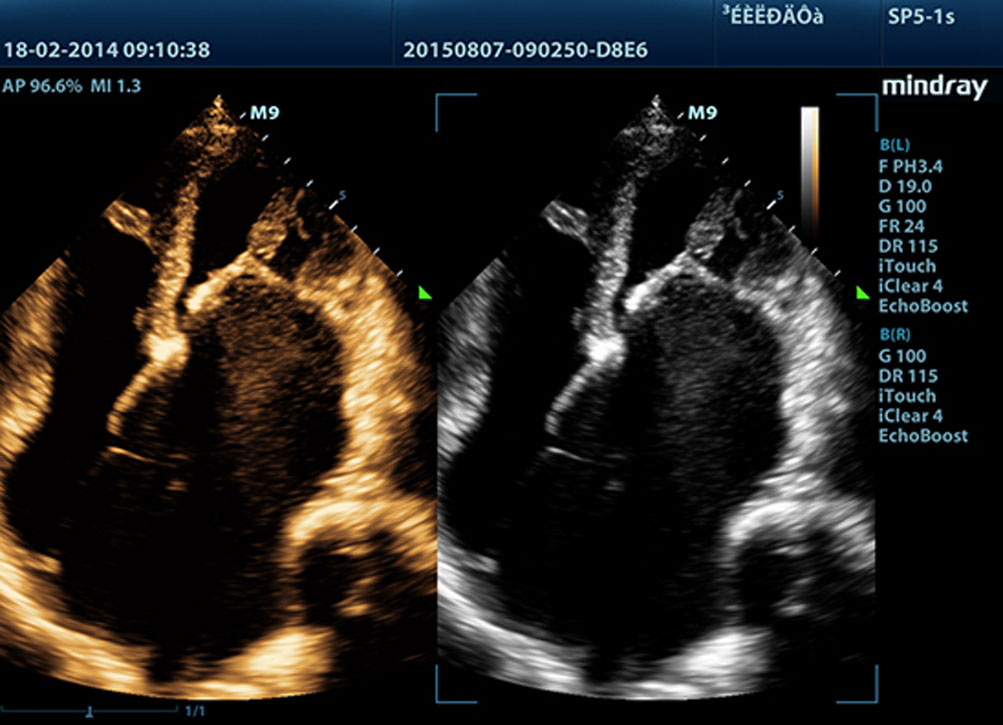

Echo Boost?

Unikalna technologia adaptacyjnego przetwarzania sygna?u Firmy Mindray z inteligentnym wykrywaniem echa, zaprojektowana do wykorzystywania informacji o stosunku ?sygna? / szumâ w celu wzmocnienia s?abych sygna?Ãģw echa, przy jednoczesnym t?umieniu zak?ÃģceÅ, zapewnia bardziej zrÃģwnowa?on? jasno?? obrazu i lepsz? wizualizacj? warstw tkanki mi??nia sercowego.